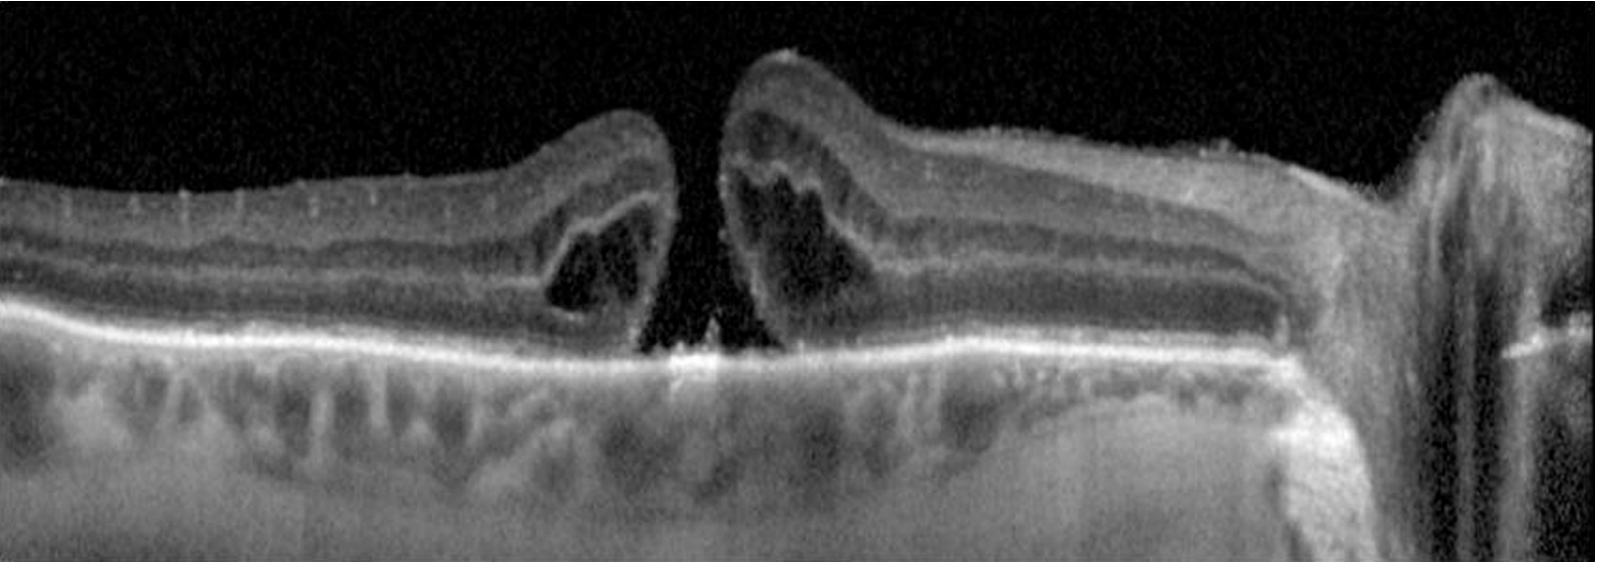

OCT appearance of macular hole:

Macular hole OCT

• OCT is the key test for confirmation and staging

1. Optical Coherence Tomography (OCT)

Gold standard for diagnosis, staging, and follow-up.